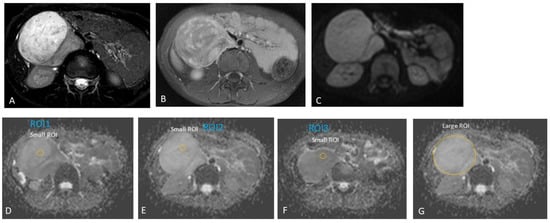

2.3.2. MRI Interpretation